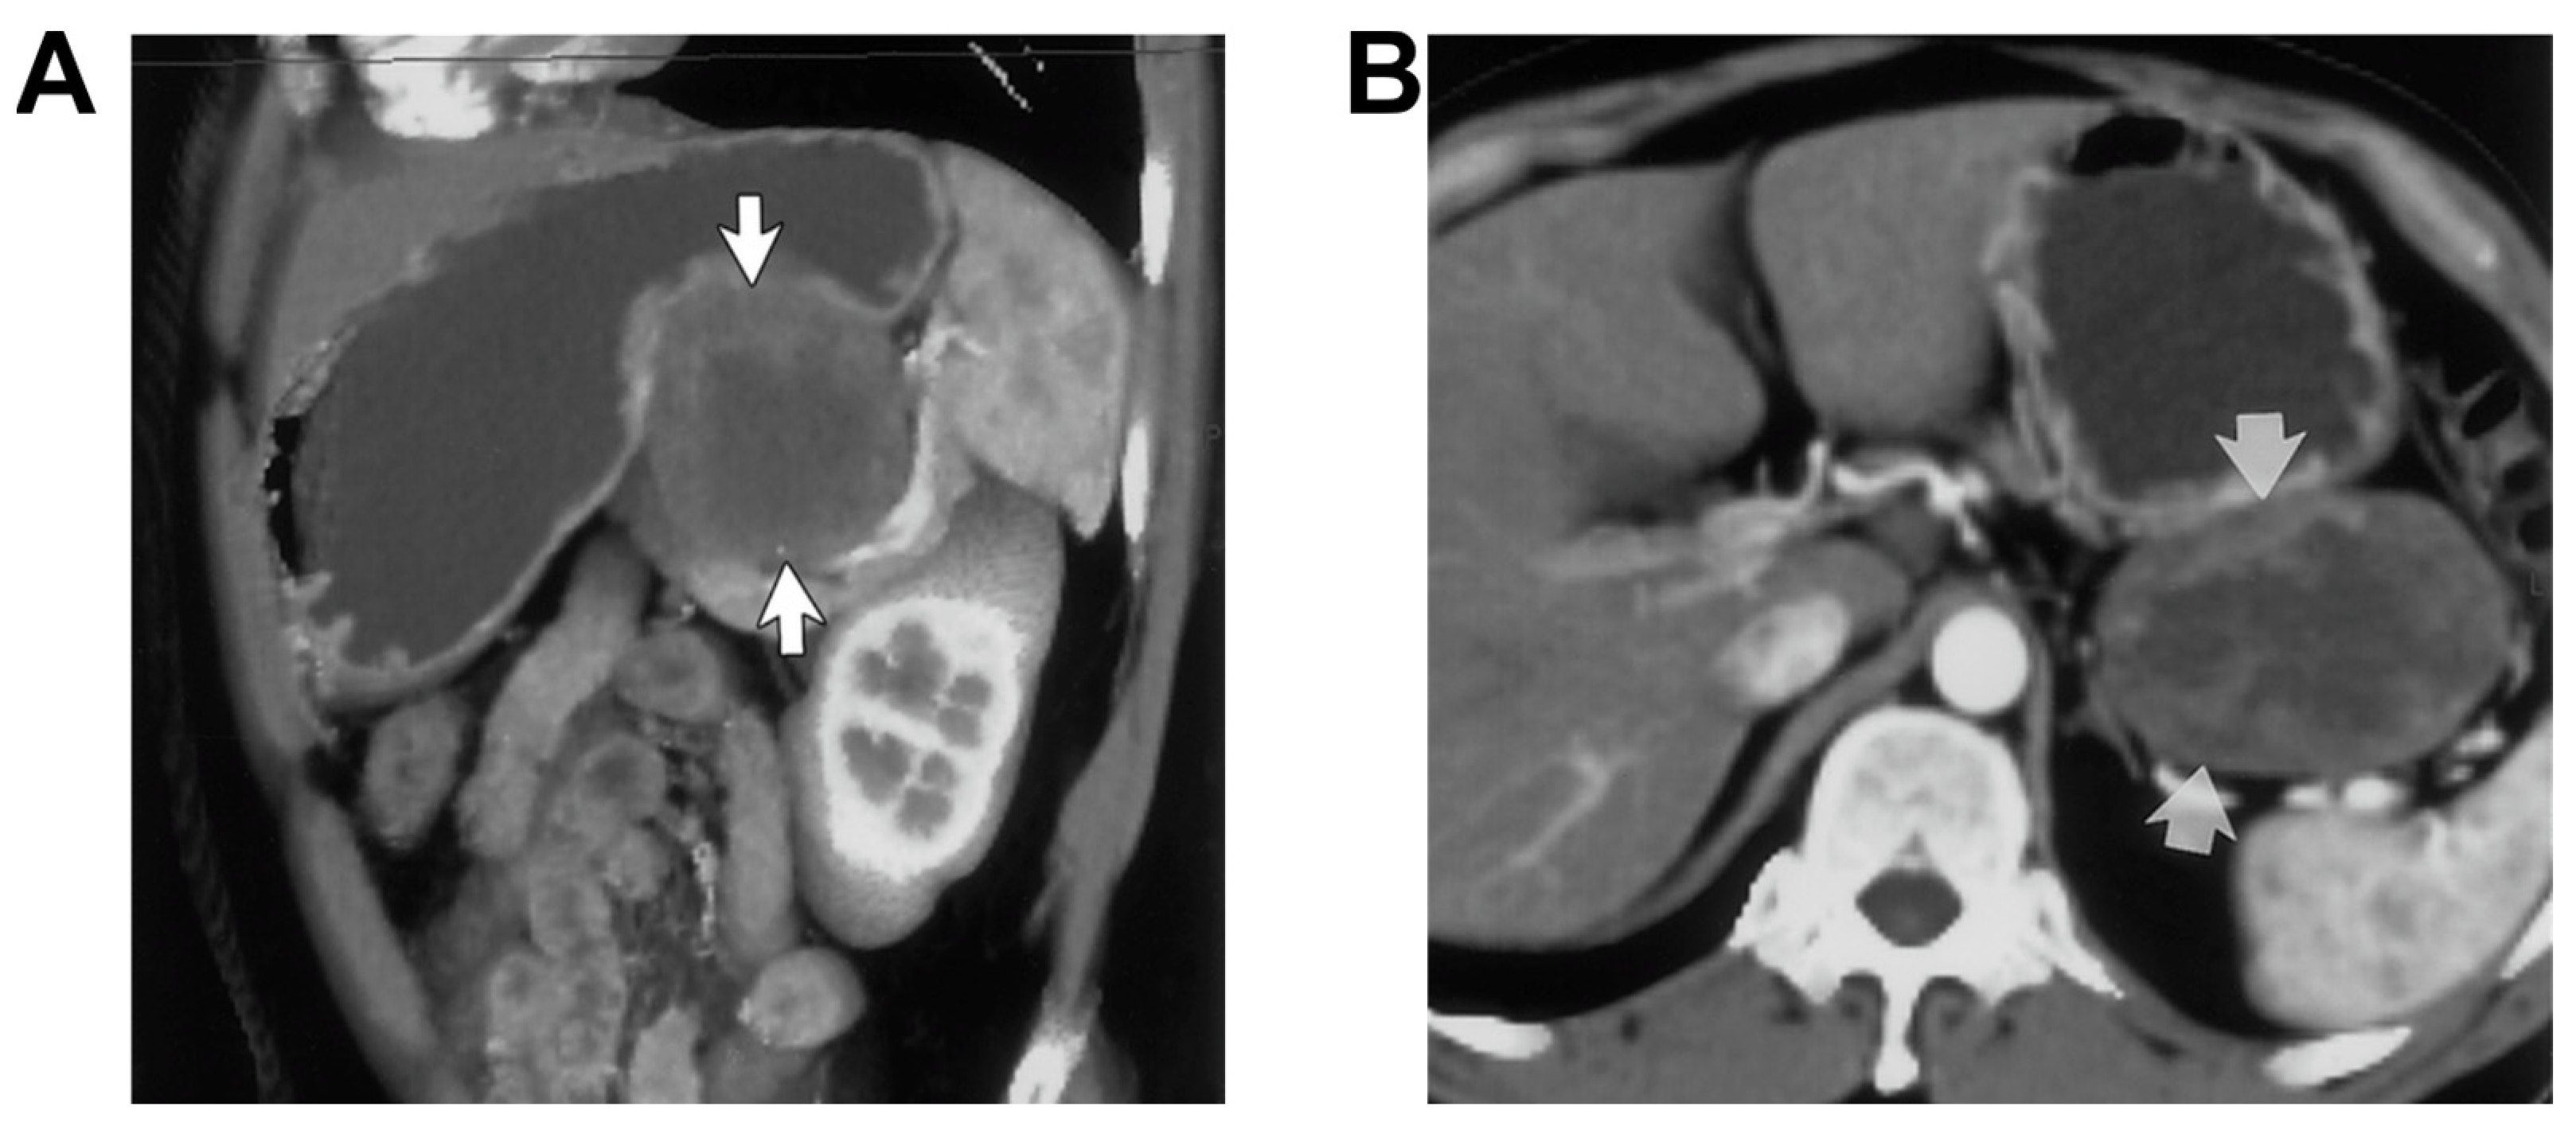

- Nigogosyan, M.; Dolinskas, C. CT demonstration of inflamed Meckel diverticulum. J. Comput. Assist. Tomogr. 1990, 14, 140–142. [Google Scholar] [CrossRef]

- Bennett, G.L.; Birnbaum, B.A.; Balthazar, E.J. CT of Meckel’s diverticulitis in 11 patients. Am. J. Roentgenol. 2004, 182, 625–629. [Google Scholar] [CrossRef] [PubMed]